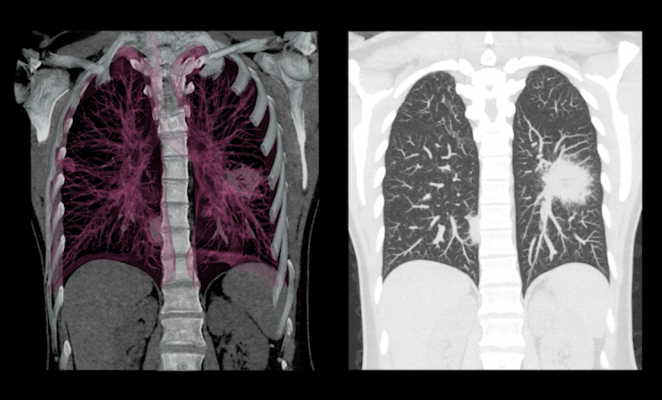

Dalam seminar tersebut, turut diperkenalkan teknologi skrining kanker paru berbasis kecerdasan buatan (Artificial Intelligence/AI) oleh PT. Sinergi Global Alkesindo .

“Standar internasional menggunakan low dose CT scan. Dengan dukungan AI, nodul kecil bisa terdeteksi lebih akurat hingga lebih dari 95 persen,” ungkapnya.

Teknologi ini mampu mengidentifikasi nodul berukuran sangat kecil yang sering terlewat dalam pemeriksaan konvensional. Sistemnya juga dapat membandingkan hasil pemeriksaan sebelumnya dan terkini secara otomatis untuk memantau perkembangan. Perangkat tersebut telah mengantongi persetujuan dari otoritas kesehatan Amerika Serikat (FDA).